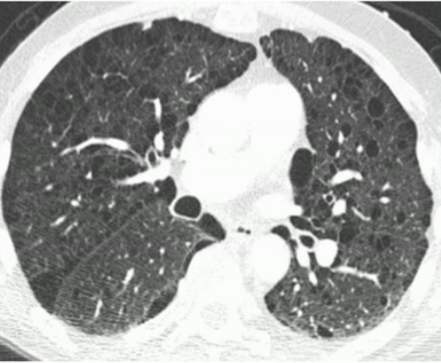

Birt-Hogg-Dub6(BHD)综合征是罕见的常染色体显性遗传肿瘤综合征。国外看病机构爱诺美康了解到,BHD综合征具有毛囊良性肿瘤(纤维囊性瘤)、肺囊肿及自发性气胸等特征,发生肾癌的风险增加7倍。BHD患者极常见的表现是纤维囊性瘤和肺囊肿(>85%)。30%的BHD患者发生不同组织学类型的肾肿瘤(平均年龄为48〜50岁),常见的是肾嫌色细胞癌和肾杂合性嗜酸细胞瘤。从BHD综合征发展而来的肾癌也有转移性的,但不常见。